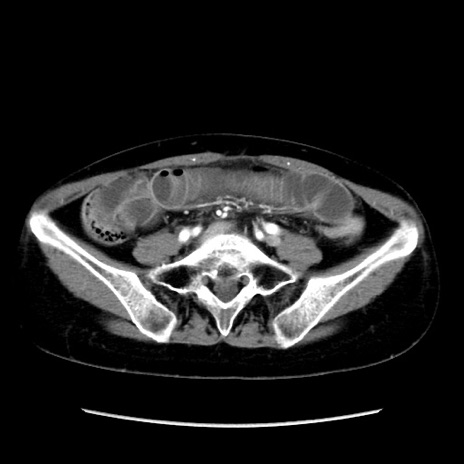

矢状断像

【症例】40歳代 女性

【主訴】上腹部痛、嘔気・嘔吐

【現病歴】約9時間前頃から急に上腹部痛、嘔気、嘔吐が出現。改善しないため救急要請。

【既往歴】子宮頚癌(広汎子宮全摘術、放射線療法)、腸閉塞

【身体所見】腹部:平坦、軟、腸雑音亢進、上腹部を中心に腹部全体に圧痛あり。

【データ】WBC 8400、CRP 0.03